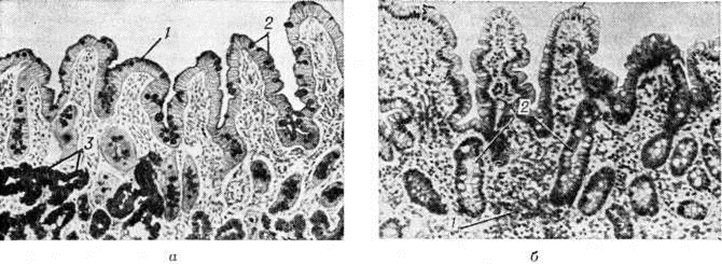

При резко выраженном Дуоденит слизистая оболочка двенадцатиперстной кишки отёчна, складки ее утолщены, расположены беспорядочно, строма слизистой оболочки густо инфильтрирована лимфоидными клетками (рисунок 2). Выявляются дистрофические изменения в кишечном эпителии: цитоплазма клеток слизистой оболочки вакуолизирована (смотри полный свод знаний Вакуолизация), значительно увеличено количество бокаловидных энтероцитов (смотри полный свод знаний Бокаловидные клетки). Усиленная инфильтрация распространяется на глубже лежащие слои. Дуоденальные железы с расширенными просветами сливаются между собой, образуя крупные кисты. Дуоденит с атрофией слизистой оболочки характеризуется сглаженностью рельефа слизистой оболочки за счёт укорочения и расширения кишечных ворсин, уплотнением кишечного эпителия с резким уменьшением числа бокаловидных энтероцитов, увеличением глубоких крипт (рисунок 3). Установлено, что слизистая оболочка луковицы значительно чаще и в большей степени подвергается патологический изменениям (проксимальный Дуоденит), чем дистальные отделы двенадцатиперстной кишки (дистальный Дуоденит). Клиническая картинаПо клинической., течению различают острый и хронический дуоденит. Острый дуоденит в большинстве случаев сочетается с воспалительными заболеваниями слизистой оболочки желудка и тонкой кишки (смотри полный свод знаний: Гастрит, Энтерит, энтероколит); он протекает по типу острой пищевой токсикоинфекции. Больные жалуются на тошноту, рвоту пищевыми массами с примесью желчи, головную боль, слабость, недомогание; характерны склонность к гипотензии и ортостатическому коллапсу (смотри полный свод знаний). При пальпации живота обнаруживается болезненность над пупком справа. При дуоденальном зондировании (смотри полный свод знаний) в кишечном содержимом обнаруживают слизь, слущённый эпителий, а в некоторых, особенно тяжёлых случаях — кровянистые массы. Хронический дуоденит очень редко бывает следствием острого, чаще он развивается первично и характеризуется жалобами больного на постоянные боли в верхней части живота справа на уровне пупка и диспептические явления. Боли усиливаются натощак или спустя 1½—2 часа после приёма пищи, нередко беспокоят больных в ночное время («ночные» боли), иногда наиболее интенсивны во второй половине дня, к вечеру. У некоторых больных наблюдается чувство тяжести, «сосания» в животе, которое усиливается после еды. Наиболее частые диспептические явления — изжога, горечь во рту, отрыжка воздухом или кислым желудочным содержимым, тошнота и рвота. После отрыжки воздухом и рвоты иногда отмечается значительное облегчение. Больные Дуоденит часто страдают запорами (смотри полный свод знаний), их беспокоит головная боль, головокружение, приступы адинамии и усталости (для этих симптомов характерна периодичность появления — через 2—3 часа после приёма пищи). С течением времени больные теряют в весе, кожные покровы приобретают бледную окраску, отмечаются нарушения белкового, витаминного и электролитного обмена (смотри полный свод знаний: Азотистый обмен, Витаминная недостаточность, Водно-солевой обмен). Течение хронический Дуоденит цикличное: фаза обострения сменяется фазой ремиссии. Обострение заболевания обычно длится от 1 до 2 месяцев, чаще наблюдается весной или осенью, хотя и с меньшей закономерностью, чем при язвенной болезни. Диагноз ставят на основании тщательного клин, обследования, включающего исследование секреторной функции желудка, дуоденального содержимого, рентгено л. исследование и особенно дуоденоскопию (смотри полный свод знаний), иногда с прицельной биопсией и последующим морфологически исследованием биопсированного материала. Лечение определяется характером общих и местных анатомо-функциональных нарушений. Больным острым Дуоденит показано промывание желудка слабым р-ром перманганата калия с последующим введением 25—30 грамм сульфата магния, растворенного в стакане воды, постельный режим, голодная диета в течение 1 — 2 дней. При необходимости (при спазмах, болях) назначают атропин, метацин, а также ганглерон, кватерон. Постепенное расширение диеты рекомендуется со вторых-третьих суток. При сопутствующих Дуоденит в первую очередь проводят лечение основного заболевания, при первичных — терапия направлена на сокращение фазы обострения процесса. Лечение может быть проведено амбулаторно, но при выраженной клин, картине показано пребывание в стационаре. В период обострения рекомендуется соблюдение механически и химически щадящей диеты, богатой белками, жирами, витаминами (смотри полный свод знаний: Лечебное питание, столы лечебного питания); медикаментозное лечение — назначение холинолитических (атропин, платифиллин, спазмолитин, арпенал, метацин, фубромеган) и ганглиоблокирующих (ганглерон, кватерон) средств. Ганглерон назначают в виде 1,5% раствора по 2 миллилитров внутримышечно 3 раза в день в течение 2—3 недель; кватерон — по 30—50 миллиграмм в порошках или в виде 0,2% раствора по 1 — 2 столовой ложке 3—4 раза в день в течение 4 недель. Для стимуляции трофических процессов целесообразно назначение белковых гидролизатов и других биостимуляторов (аминопептид, аминокровин) в молодом возрасте —250 миллилитров внутривенно или подкожно капельно 2 раза в неделю в течение 2—3 недель в комбинации с нероболом, ретаболилом. В нетяжёлых случаях можно ограничиться инъекциями алоэ. Рекомендуется назначение парентерально витаминов группы В в комбинации с аскорбиновой кислотой. При выраженной активности секреторного аппарата желудка показано применение антацидных средств короткого и длительного действия (гидрокарбонат натрия, окись магния, гидроокись алюминия, трисиликат магния, алмагель, фосфалугель). Антацидные средства короткого действия целесообразно назначать после еды; алмагель и фосфалугель назначают за 20—30 минут до приёма пищи. Длительность применения антацидных средств 2—3 недель. Больным хронический Дуоденит в фазе ремиссии или спустя 2—3 месяцев после последнего обострения показано курортное лечение с применением внутрь минеральных вод, грязелечение и минеральные ванны. Больные хронический Дуоденит должны находиться под диспансерным наблюдением с периодическим рентгенологическое и эндоскопическим обследованием. Им показано проведение курсов противорецидивного лечения (смотри полный свод знаний Язвенная болезнь). ПрогнозПри адекватном лечении может наступить полное выздоровление, однако нередко Дуоденит принимает хронический рецидивирующий характер. Профилактика—своевременная ликвидация очагов инфекции, соблюдение рационального режима питания, своевременное лечение заболеваний, способствующих развитию Дуоденит Флегмонозный дуоденит (синонимы флегмона двенадцатиперстной кишки)— острое гнойное воспаление стенки двенадцатиперстной кишки. Впервые описано в 1905 год Дейтельмозером (Deutelmoser). Флегмонозный Дуоденит — редкое самостоятельное заболевание, составляет не более 15% всех флегмонозных поражений пищеварительного тракта. Этиология и патогенезФлегмонозный Дуоденит развивается у ослабленных больных со сниженной бактерицидной способностью желудочного сока. Различают первичные (энтерогенные) и вторичные флегмоны двенадцатиперстной кишки. Причиной первых служит микробная флора (стафилококки, стрептококки, кишечная палочка), проникающая через слизистую оболочку двенадцатиперстной кишки. Проникновению возбудителей инфекции способствуют язвы двенадцатиперстной кишки, повреждение слизистой оболочки инородными телами, желчными камнями, паразитами и другие, дивертикулы, рак. Возможно распространение инфекции по лимфатических, путям подслизистого слоя при наличии флегмоны желудка или тощей кишки. Вторичные флегмонозные Дуоденит возникают вследствие гематогенного заноса микробов из гнойного очага: фурункула, карбункула, бронхоэктазов. Вторичные флегмоны могут быть следствием общих инфекционных заболеваний (грипп, скарлатина, корь и другие), нагноения интрамуральной гематомы кишки. Патологическая анатомияФлегмонозный процесс чаще возникает в фиксированной забрюшинной части двенадцатиперстной кишки в области большого сосочка двенадцатиперстной кишки (фатерова соска), начинается в подслизистом слое и распространяется вдоль кишки на глубокие слои кишечной стенки. В процесс рано вовлекаются лимфатических пути. По характеру патологический процесса различают острый и хронический флегмонозный Дуоденит, по распространённости — диффузный и ограниченный; последний может закончиться самоизлечением вследствие прорыва гнойника в просвет кишки. В течении флегмонозного Дуоденит различают инфильтрирующую, абсцедирующую и грануляционно-рубцовую фазу флегмоны (смотри полный свод знаний:). Поражённая кишка ярко-красного или багрового цвета; стенка её на разрезе диффузно пропитана гноем; воспаление сопровождается выраженным лимфаденитом (смотри полный свод знаний:), иногда с абсцедированием. Процесс может завершиться расплавлением стенки кишки, переходом гнойной инфекции на забрюшинное пространство (смотри полный свод знаний) или прорывом гноя в свободную брюшную полость с развитием ограниченного или разлитого перитонита. Клиническая картинаЗаболевание чаще начинается бурно, с явлений непроходимости двенадцатиперстной кишки или перитонита (смотри полный свод знаний). Состояние больных быстро становится тяжёлым. Характерны схваткообразные боли в правой половине живота, сопровождающиеся частой рвотой; в результате отёка большого сосочка двенадцатиперстной кишки рано развивается желтуха (смотри полный свод знаний). Заболевание сопровождается высокой температурой с ознобами, частым пульсом, лейкоцитозом с преобладанием нейтрофильных лейкоцитов и появлением в их протоплазме токсической зернистости. При пальпации живота отмечается умеренное или слабовыраженное напряжение мышц брюшной стенки при резкой болезненности в правом подреберье или эпигастрии. Рано появляется положительный симптом Щеткина—Блюмберга (смотри полный свод знаний Щеткина — Блюмберга симптом). При переходе процесса на забрюшинную клетчатку возникают боли в пояснице и ряд симптомов, характерных для острого панкреатита (смотри полный свод знаний). Флегмонозный Дуоденит осложняется перитонитом, поддиафрагмальным и подпечёночным абсцессами, флегмоной забрюшинной клетчатки, гнойным плевритом (смотри полный свод знаний), медиастинитом (смотри полный свод знаний:), сепсисом (смотри полный свод знаний). В случае ликвидации воспалительных явлений может развиться рубцовая стриктура двенадцатиперстной кишки. Лечение оперативное: после лапаротомии — мобилизация двенадцатиперстной кишки по Кохеру (смотри полный свод знаний Двенадцатиперстная кишка), обкалывание забрюшинной клетчатки раствором антибиотиков, подведение тампонов и дренажей к двенадцатиперстной кишке и в забрюшинное пространство. При наличии перитонита — лечение его по общепринятым принципам. В некоторых случаях для отключения поражённой двенадцатиперстной кишки и раннего кормления накладывают еюностому (смотри полный свод знаний: Энтеростомия). Прогноз, как правило, неблагоприятный. Смотри, полный свод знаний Перидуоденит.